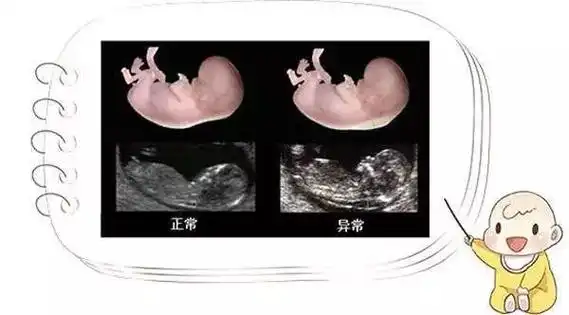

就可以了不过,建议最好是怀孕12-13周的时候再测,有90%以上的准确率

孕囊大小38*23mm,男宝宝7周1天,孕囊大小:29*19mm,男孩5周6天,孕囊